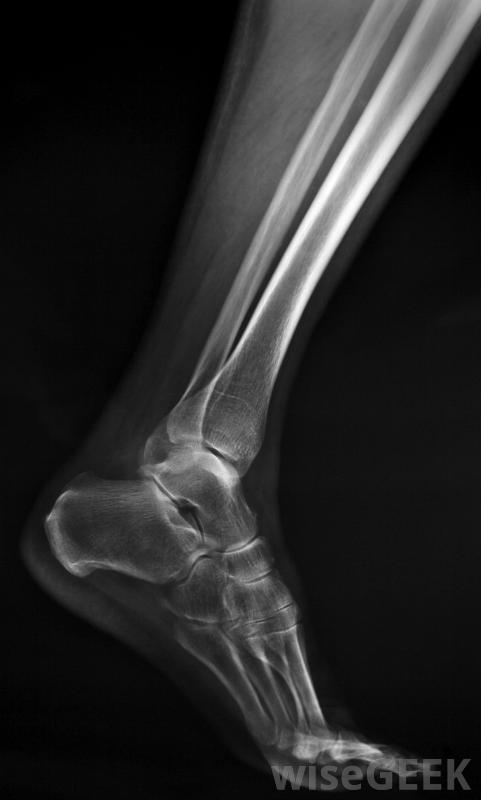

生长中的儿童长骨一端的骨折,包括其生长板,称为骨骺骨折。未成熟长骨每端附近的软骨盘使骨骼生长。这些生长组织区域称为骺板,在儿童成熟至成年时变硬。骨骼中的生长板是骨骼结构最薄弱的部位,容易受伤,称为骨折。这种骨折...

生长中的儿童长骨一端的骨折,包括其生长板,称为骨骺骨折。未成熟长骨每端附近的软骨盘使骨骼生长。这些生长组织区域称为骺板,在儿童成熟至成年时变硬。骨骼中的生长板是骨骼结构最薄弱的部位,容易受伤,称为骨折。这种骨折有时被称为Salter骨折或Salter Harris骨折。

儿童在被诊断为骨骺骨折之前,可能需要接受多次X光检查。一种更罕见的骨折骨骺和生长板与干骺端分离的部分属于III型骨骺骨折。青少年最容易遭受这种损伤。它通常发生在胫骨下端,胫骨是小腿的长骨之一。这种类型的骨折有时需要手术治疗骨折尽管如此,如果骨骺分离部分的血液供应得以维持,骨骼正常生长的机会仍然很大。

骨骺骨折常见于胫骨下端骨骺板压缩性骨折是罕见的,通常包括骨头末端和生长板的压碎,这种损伤属于V型骨骺骨折,预后差,最典型的是导致生长发育不全,很难被发现,而且通常在正常生长障碍变得明显之前仍然无法被诊断出来。这类骨折通常需要外科治疗,而且通常还需要后期的矫正手术